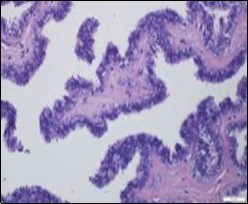

Figure 1.Ciliated cutaneous cyst lined by pseudostratified ciliated columnar epithelium and a supporting fibro-connective tissue stroma 11.

Typically, cutaneous ciliated cyst is a simple cyst which demonstrates a layering of pseudostratified ciliated columnar epithelium recapitulating conventional epithelial lining of the fallopian tube. As the cutaneous ciliated cyst demonstrates a morphological similarity to the fallopian tube lining epithelium, a Mullerian origin is indicated. Gross examination of cutaneous ciliated cyst depicts a solitary, mobile, non-tender, fluctuant, firm or soft to cystic lump with a fibrous wall and abundant amount of circumscribing adipose tissue. Cutaneous ciliated cysts are of a variable dimension. Cut surface usually displays a unilocular cyst impacted with clear, serous fluid, an attenuated smooth, greyish/ white cyst wall incorporated with incomplete septa traversing the cyst 6, 7.

Morphological analysis preponderantly demonstrates a solitary, uni-locular or multi-locular cyst of Mullerian origin with an epithelial lining recapitulating the epithelium of fallopian tube.

Cutaneous ciliated cyst is layered with a singular layer of ciliated epithelial cells which are chiefly constituted by cuboidal to columnar epithelium, traversed by partially configured fibrous tissue septa with an admixture of randomly dispersed, intraluminal papillary projections akin to those cogitated in the fallopian tube. Superimposed epithelium is inundated with well vascularized, parallel bundles of collagen although smooth muscle is absent 7, 8.